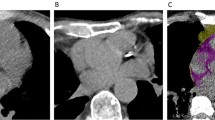

CTEAT, defined as the total amount of adipose tissue between the surface of the heart and the visceral layer of the pericardium, was measured by volumetry on short-axis slices with a thickness of 0.75 mm, ranging from the level of the pulmonary bifurcation to the apex and within a threshold range of -190 to -30 Hounsfield units (HU) to determine the total volume of tissue [17]. The adipose tissue around the coronary artery is part of the EAT and was defined as the attenuation coefficient of the fat tissue voxels within a distance from the coronary arterial wall equal to the corresponding vessel diameter. The attenuation coefficient was calculated separately for the right coronary artery (RCA), left anterior descending artery (LAD), and left circumflex artery (LCX) using the coronary artery analysis module [18].

The cardiac mass was determined using the syngo.via cardiac analysis module, which automatically traces the endocardial and epicardial borders to generate the volume of the heart. The myocardial volumes were converted to left ventricle mass (M) by assuming a constant tissue density of myocardium (1.05 g/cc). CTV/M was calculated by dividing the luminal volume of the coronary artery by the myocardial mass of the heart [9, 19]. The luminal volume of the coronary artery was extracted by a deep learning calculation method on the workstation. In this study, the right coronary artery was selected for coronary lumen volume analysis given its simplicity and thick diameter in the Chinese population.

Except for CTV/M (26.2% [IQR, 24.4; 27.8] vs. 22.0% [IQR, 21.0; 24.0], P < 0.01), the CCTA-derived parameters in the healthy groups were significantly lower (P < 0.05) than those in the non-ICHF group (Table 1). In non-ICHF, the volume of adipose tissue around the proximal LAD (-79.8 HU [IQR, -78.2; -81.3]) was higher than that around the RCA (-68.9 HU [IQR, -65.3; -73.1]) and LCX (-73.3 HU [IQR, -67.1; -75.4]) (Table 1, Fig. 2).

There was a moderate to strong correlation between healthy patients and non-ICHFHF patients in the attenuation of the PCAT of the LAD (r = 0.55; P < 0.0001), the right circumflex artery and LCX (r = 0.422; P < 0.0001), the coronary lumen volume (r = -0.57; P < 0.0001) and CT-derived cardiac V/M ratio (r = -0.72; P < 0.0001) (Supplementary Fig. 1).